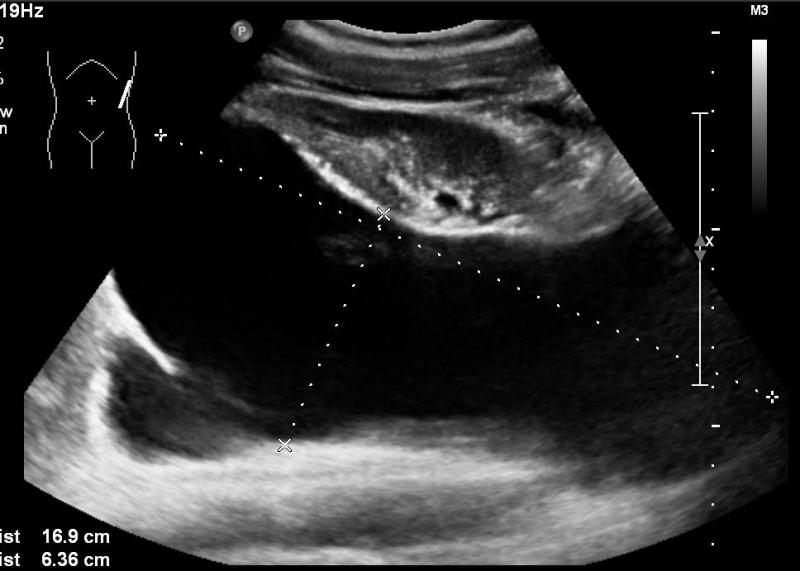

Rozpoznanie: W badaniu USG uwidoczniono wgłobienie krętniczo-kątnicze (białe strzałki).